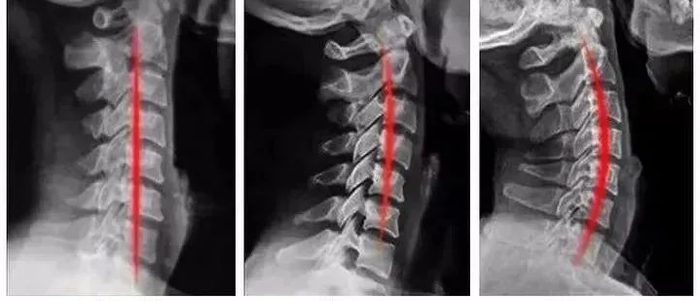

健康的颈椎是有一个前凸的生理曲线的,曲度变直、反弓都是不健康的表现!